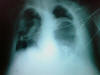

Insuficiencia cardiaca.

ICC